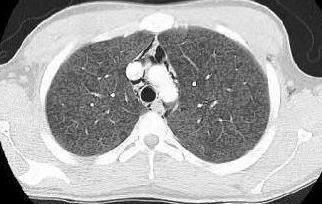

Chest x-ray films revealed diffuse parenchymal haziness and air tracking into the soft tissues of the neck, axilla, and the mediastinum (Figure 1). CT scan of the thorax revealed diffuse homogeneous distribution throughout both lungs of ground-glass opacities that suggested subacute hypersensitivity pneumonitis. Extensive pneumomediastinum (Figure 2a), and cervical emphysema (Figure 2b) were also noted on CT scan.